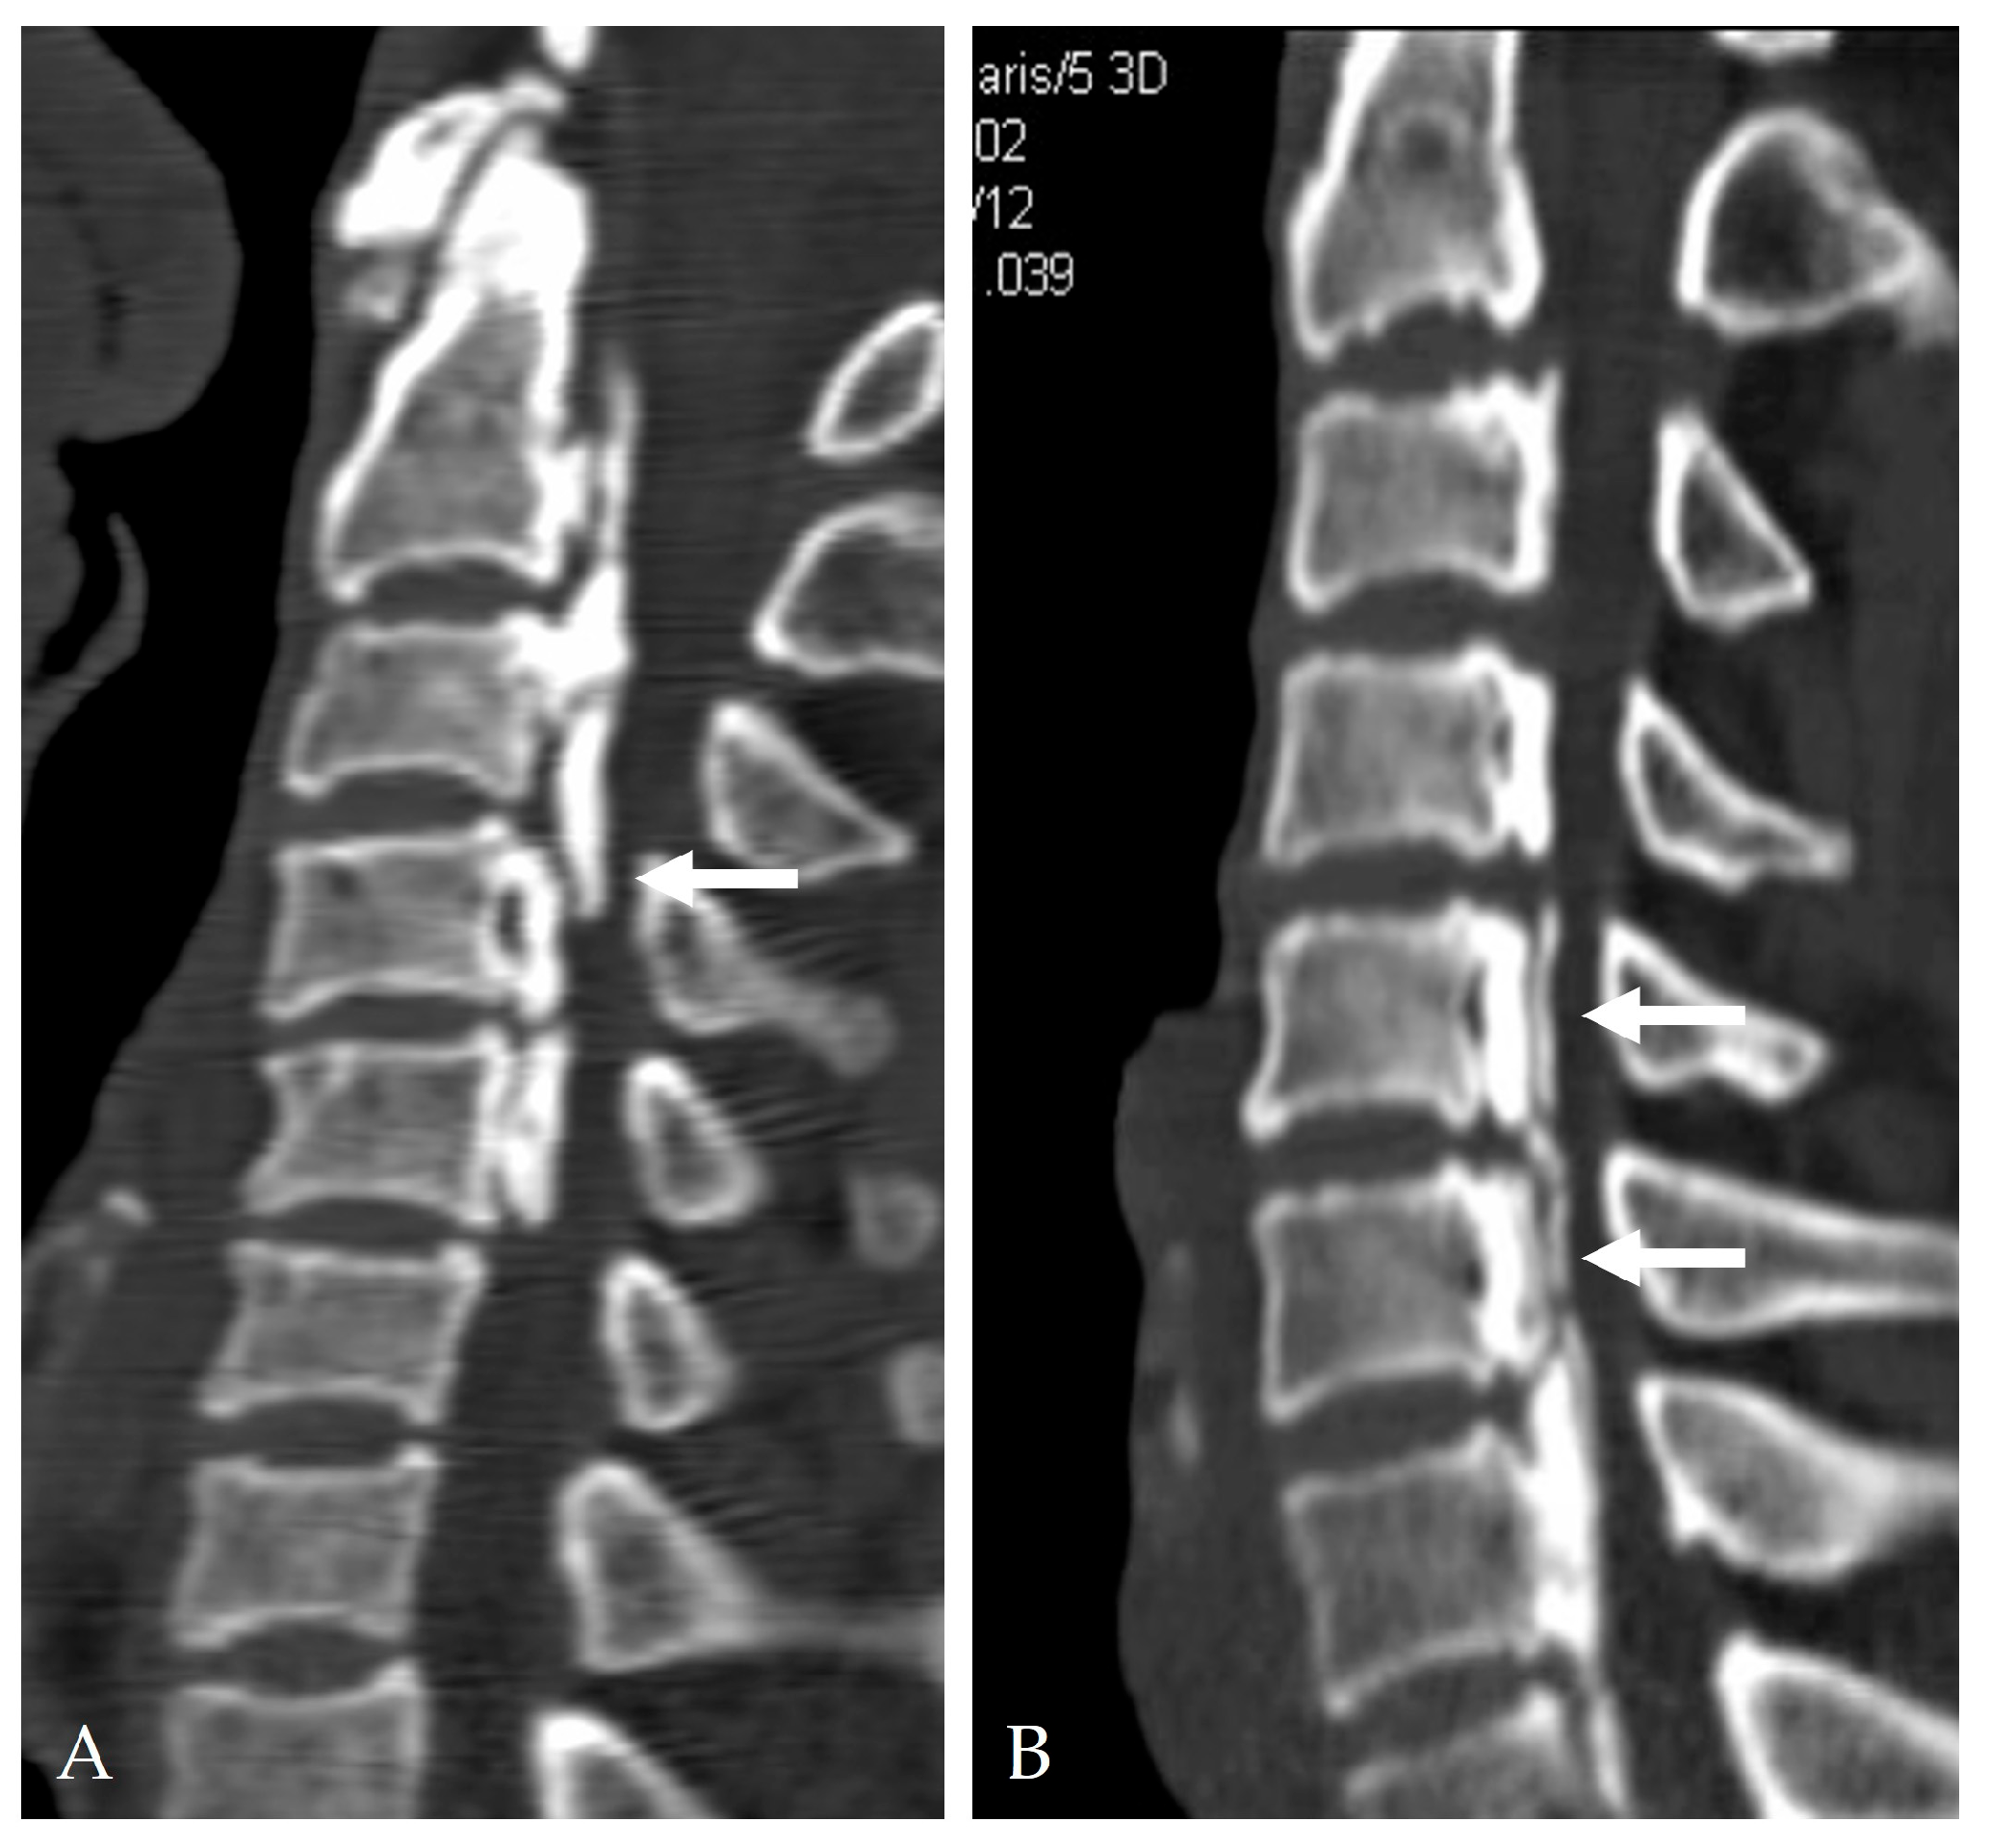

2.4. Radiologic Predictors and Morphological Correlates

2.5. Disease-Specific Factors: Dural Ossification and Adhesion Severity

3.3. Role of Dural Ossification (DO) in Leak Formation

- Min, J.H.; Jang, J.S.; Lee, S.H. Clinical significance of the double-layer sign on computed tomography in OPLL. Neurosurgery 2007, 61, 118–121. [Google Scholar] [CrossRef]

- Yang, H.; Yang, L.; Chen, D.; Wang, X.; Lu, X.; Yuan, W. Implications of different patterns of the “double-layer sign” in cervical OPLL. Eur. Spine J. 2015, 24, 1631–1639. [Google Scholar] [CrossRef]